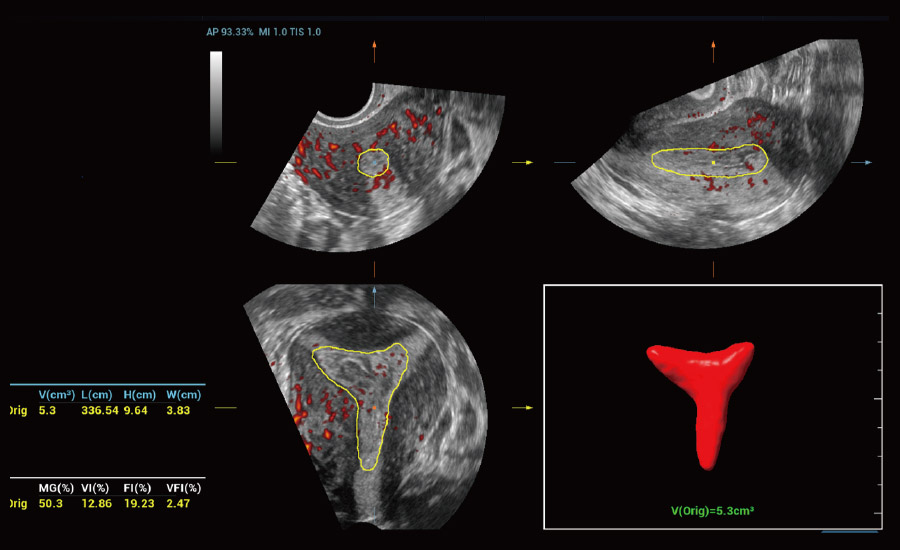

UMA (angiografia ultramicroscĆ³pica)

A tecnologia inovadora elimina as limita??es das tradicionais imagens com Doppler. Com resolu??o espacial e sensibilidade de fluxo ultra-altas, permite a detec??o de perfus?es de fluxos muito sutis e lentos, ampliando assim a aplica??o clĆnica da avalia??o qualitativa e quantitativa do ultrassom no cĆ©rebro fetal, rins, placentas, endomĆ©trios, ovĆ”rios etc.

UMA 3D ā Fluxo sanguĆneo perifolicular

Por meio da combina??o de algoritmos avan?ados e do conhecimento especĆfico da regi?o, a inovadora solu??o Smart Scene permite a identifica??o automĆ”tica das caracterĆsticas do tecido e fornece diagnĆ³stico especĆfico dos Ć³rg?os com informa??es completas. Com base na identifica??o automĆ”tica de cenĆ”rios, a solu??o realiza n?o apenas a varredura 2D inteligente com configura??es e medidas automĆ”ticas, mas tambĆ©m oferece informa??es 3D abrangentes em todas as etapas, desde a otimiza??o de imagens volumĆ©tricas atĆ© a difĆcil obten??o de planos 2D, e a quantifica??o durante todo o procedimento. Ele ajuda a reduzir em grande parte a dependĆŖncia de habilidades clĆnicas, ao mesmo tempo que aumenta a precis?o, a confian?a e a eficiĆŖncia no diagnĆ³stico.